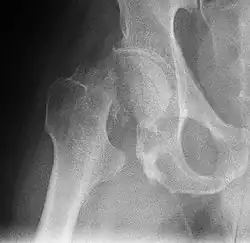

Die Schenkelhalsfraktur (SHF) oder der Schenkelhalsbruch, Kurzform für Oberschenkelhalsbruch oder Oberschenkelhalsfraktur, ist ein hüftgelenksnaher Knochenbruch (Fraktur) des Halses (Collum) vom Oberschenkelknochen (Femur). Diese Fraktur entsteht meist durch Sturz auf die Seite. Sie tritt besonders im hohen Lebensalter auf (→ Sturz im Alter) und ist dann, bedingt durch Osteoporose, häufiger bei Frauen als bei Männern.

Die mediale Schenkelhalsfraktur ist die am häufigsten auftretende Fraktur des Oberschenkelknochens.[4] Es handelt sich dabei um einen Bruch des Schenkelhalses nahe oder direkt am Femurkopf. Im Gegensatz zur lateralen Schenkelhalsfraktur (s. u.) liegt sie innerhalb der Gelenkkapsel (intrakapsulär). Ältere Lehrbücher benannten ausschließlich die direkt am Femurkopf liegende Fraktur als mediale Schenkelhalsfraktur und die, die lediglich im hüftgelenknahen Bereich des Schenkelhalses liegen, als „intermediär“. Diese Bezeichnung wird heute nicht mehr benutzt.